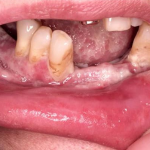

Pemphigis Vulgaris =الفقاع الشائع